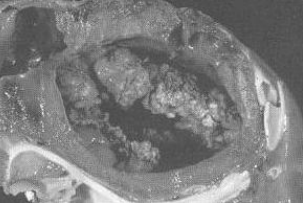

Bacterial Endocarditis in horses

Et: bacti adhere to valves, rare

aortic > mitral > tricuspid > pulmonic

Strep equi zoo, Actinobacillus equuli

Cs: intermittit fever, weight loss, murmur, inflam leukogram

Dt: Neutrophilia, high fibrinogen, Echo (visualize lesion, regurg), Bld cultures

Tx: Long-term IV antibiotics

Prognosis poor